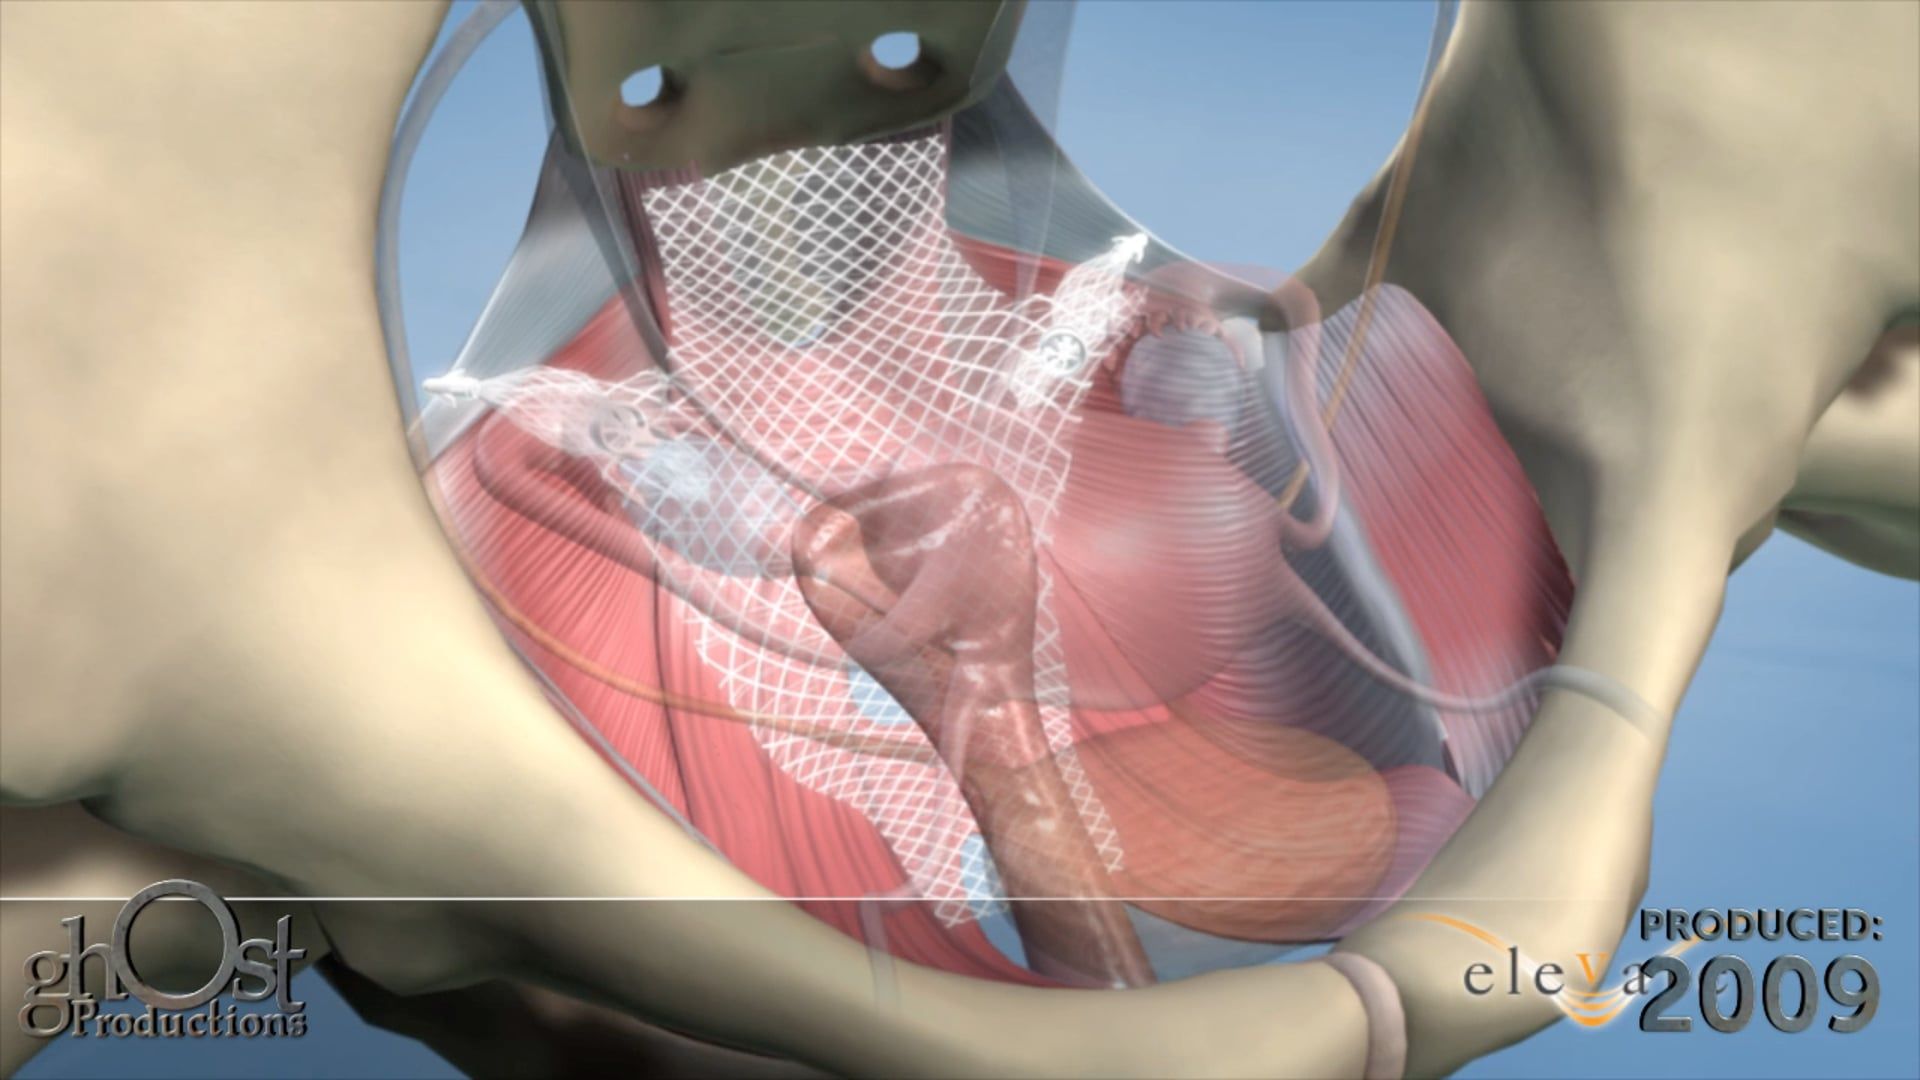

AMS partnered with Ghost Productions, a medical animation and graphics company, to create a series of animations and medical graphics that effectively communicated the benefits of their products. Ghost Productions worked closely with AMS's team to understand the mechanism of action of each product and create a visual representation of the process.

the animations and medical graphics produced by Ghost Productions proved to be instrumental in helping AMS effectively communicate the benefits of their products to their target audience. The visual aids helped potential customers and physicians understand the mechanism of action of each product and the benefits of using them to treat urological and gynecological conditions.